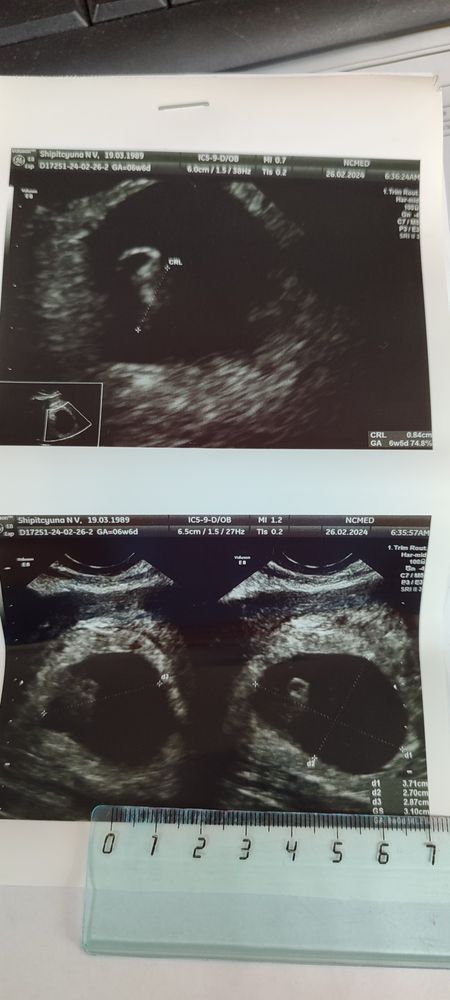

УЗИ 6недель 5 дней.

Сходила и сразу чуть чуть успокоилась. Крошку нашли, расположена хорошо, сердечко стучит. Милота.

Киста ЖТ не напрягает. Я вообще думала, что О была слева, как и обычно. Справа нигде никаких ощущений.

ВДПЯ большеват судя по таблицам. Но Узистка по этому поводу ничего не сказала. Рекомендовано УЗИ через 2 недели, т.е до скрининга.